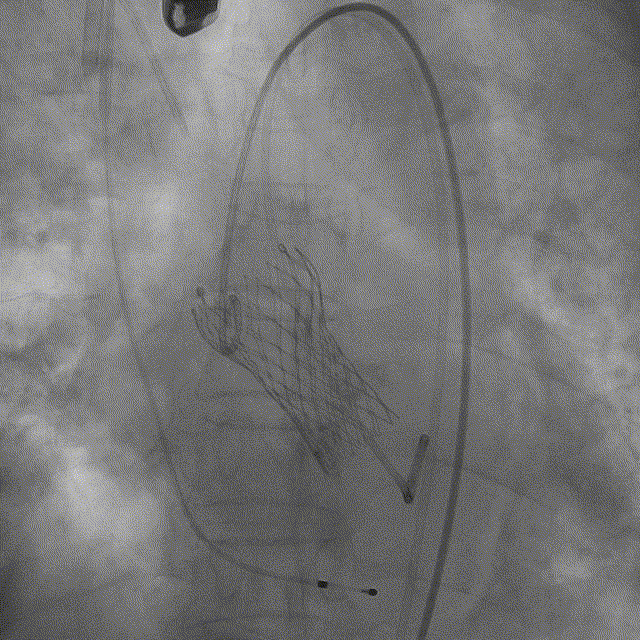

最后释放:转至三窦共面视角,调整LAO至瓣膜流入端无视差,再次评估确认后从无冠窦撤出猪尾导管,回拉导丝释放张力并做最后释放

释放完成后造影

术后TEE检查